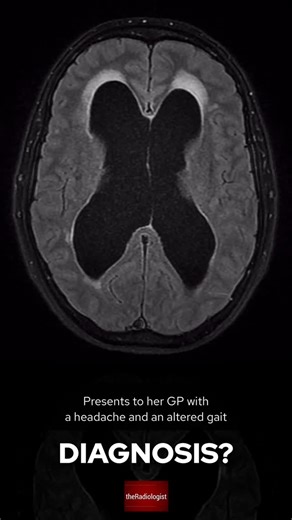

Top suggestions for Colloid Cyst Headache |